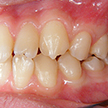

5. 術前左側

正中が相当ずれているためもあるのか、左上3番の近心辺縁隆線が左下の3番の舌側傾斜の原因となっています。下顎歯列の成長はまだ継続すると思われるので、今後より顕著となると思われます。